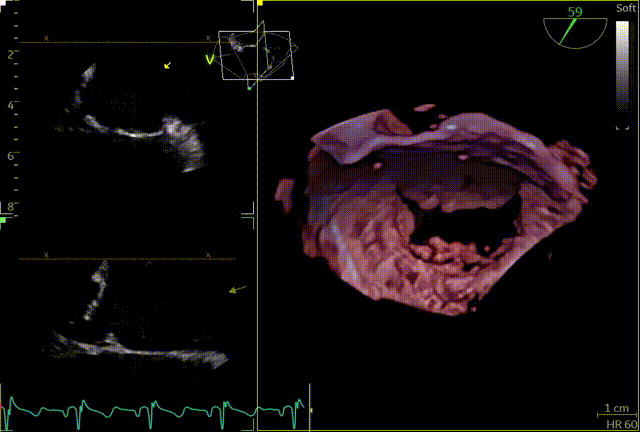

3D

3D带彩

3区gap

3D辅助辅助观察点位

穿刺高度

3D复测穿刺高度